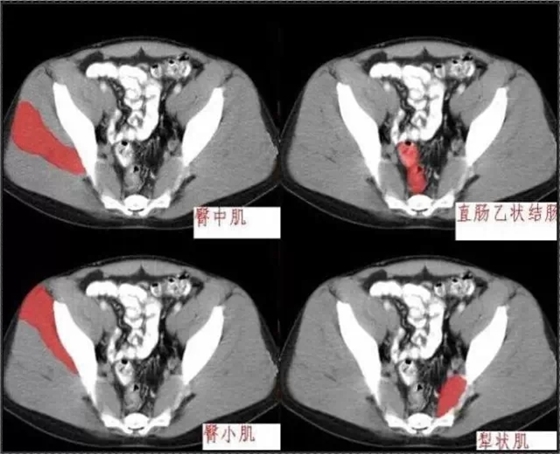

首頁(yè)口腔影像 秒懂:腹部 CT 看這篇就夠

秒懂:腹部 CT 看這篇就夠